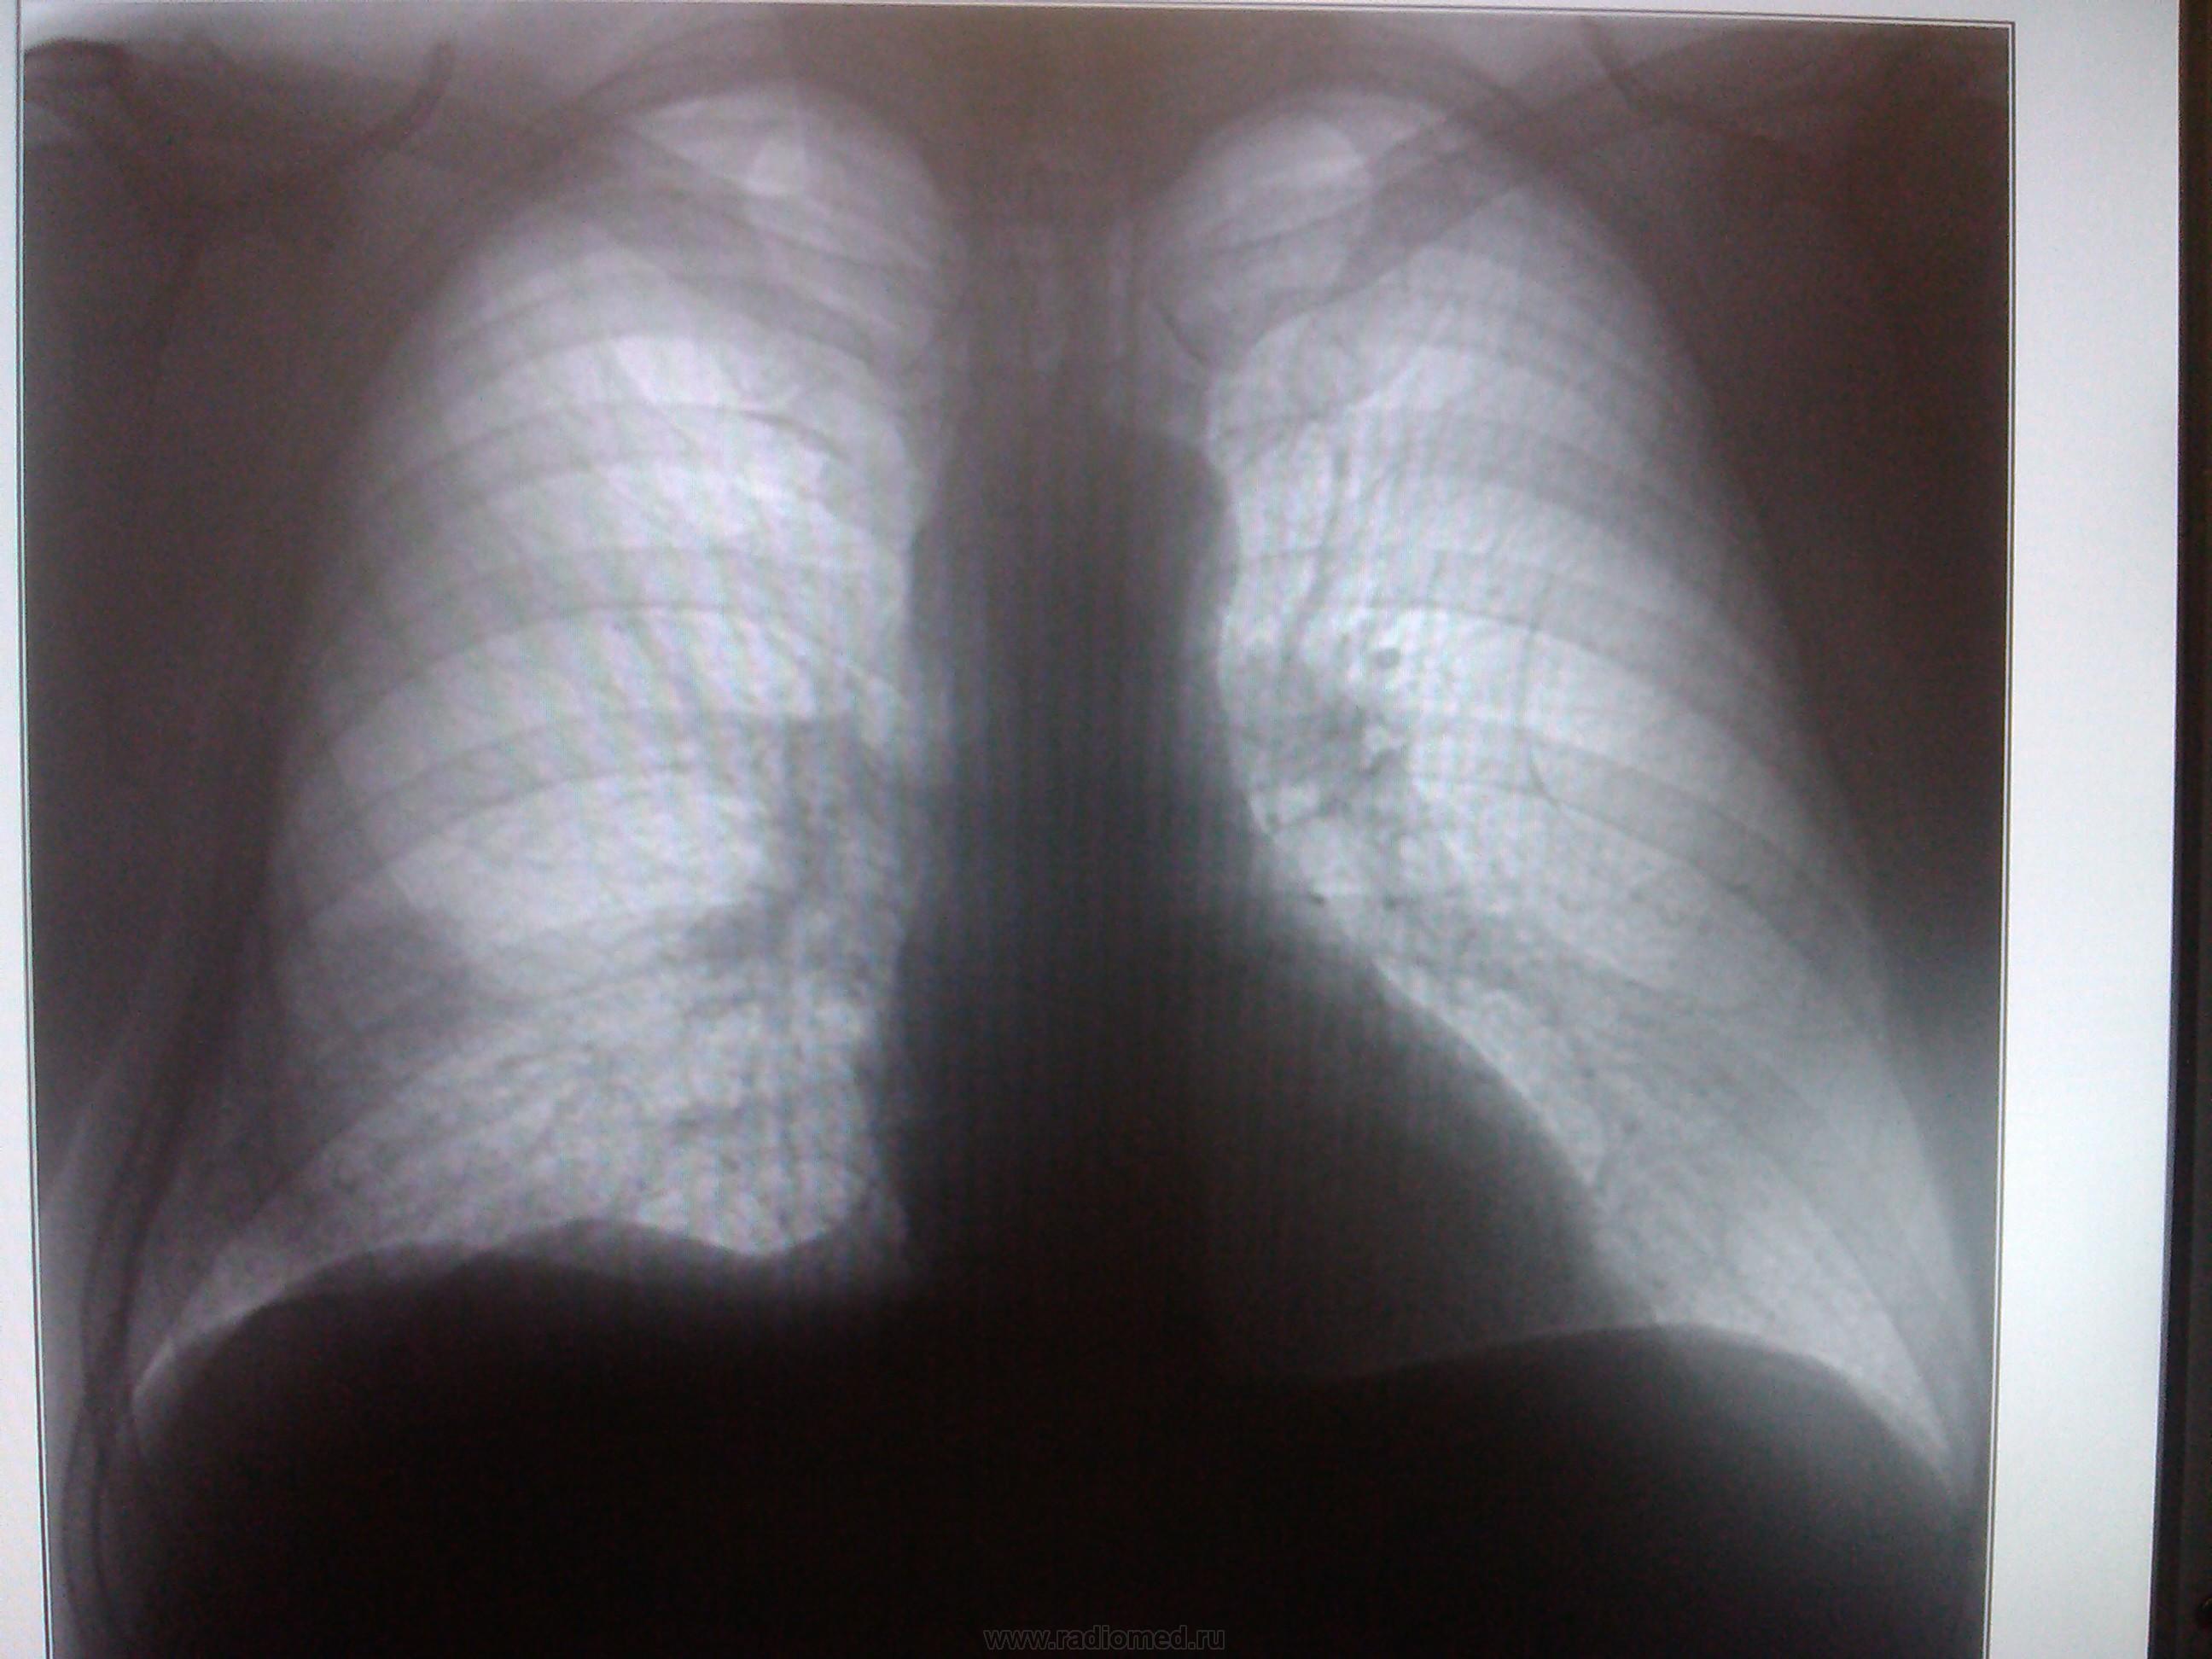

Пациент, 50 лет. Мед. осмотр. (извиняюсь за качество). Какие будут мнения?

май 2013 г.

Сначала ветку целиком не открыла, думала вопрос касается только первого снимка, высмотрела подозрительную тень на уровне 5 ребра, и правый корень не понравился. С учетом продолжения однозначно периферический

Пермферический рак нижней доли правого легкого в S9-10(учитывая отрицательную динамику за год)

Согласна с коллегами. Справа в S 10 периферическое образование, учитывая рост, более вероятно  C-r.  Cлева в среднем поле   воздушная киста